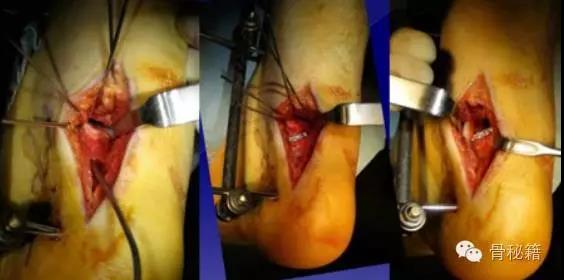

但是对于手术来说,减少损伤是必须的,一般只采用一侧入路,保护剩余的两处血供十分重要

手术入路1、内侧入路比较安全,注意大隐静脉和隐神经

骨折十分粉碎时可采用内踝截骨事先可进行螺钉的拧入,类似鹰嘴截骨

2、外侧入路

对于颈部的骨折,如果一侧钢板的位置不佳,则容易造成另外一侧的骨折裂开所以最好的固定是一侧用钢板固定,另外一侧可采用螺钉进行加压,避免另外一侧开口